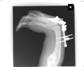

Post

Op

Xrays